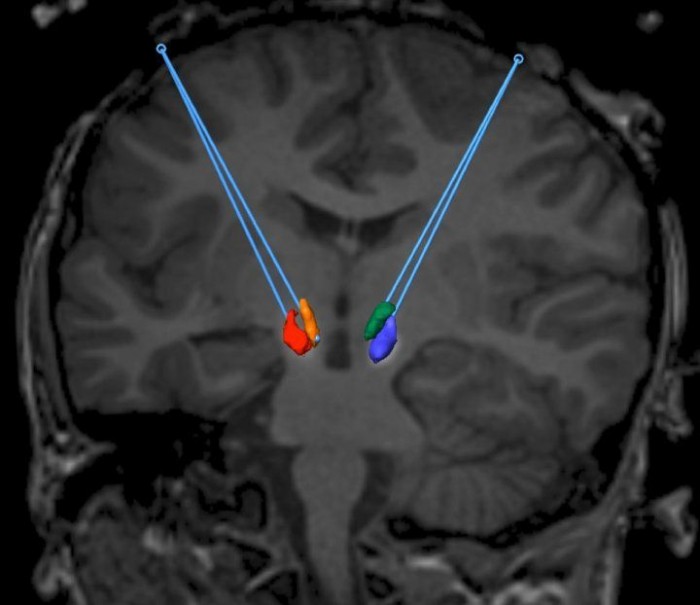

研究人员将注意力集中在中脑的两个特定区域:黑质致密区和腹侧被盖区,这两个区域都有大量产生多巴胺的神经元。

为了向这些特定的大脑区域提供基因治疗,研究人员利用了一种涉及实时磁共振成像的新手术技术。从事该项目的神经外科医生James Elder说,该手术允许外科医生在缓慢输液的过程中观察治疗在大脑中的扩散。

"真的,我们正在做的是向细胞引入不同的代码,"Elder说。“而且我们正在观察整个事情的发生过程。因此,我们不断重复核磁共振成像,我们可以看到输液在所需的细胞核内绽放。”